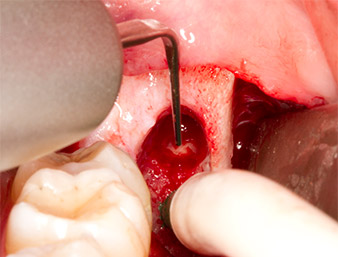

Piezomed P1

Fig. 9: The Piezomed P1 instrument is recommended by the manufacturer primarily for periodontal debridement but is also suitable for surgical purposes. Here it is placed in the root canal after minimal widening of the periodontal ligament space.

Fig. 10: Due to its slender shape, the instrument can penetrate the root canal and remove the root remnant by means of micro-oscillation (vibration).

Using an instrument for periodontal debridement (Piezomed P1), the periodontal ligament space of the radix relicta was then widened minimally (Fig. 8).

The same activated instrument was inserted into the root canal and loosened the fragment as a result of its micro-oscillating vibrations (Fig. 9, 10).

It was then possible to remove the approximately six-millimetre-long root remnant in one piece with the P1 attachment (Fig. 11).